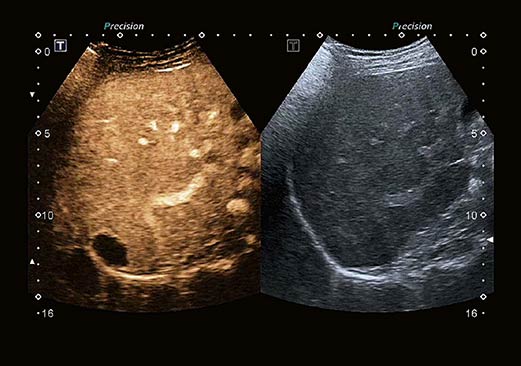

Ультразвук с контрастным усилением (CEUS). Комплексный пакет контрастной визуализации позволяет оценить динамику перфузии в широком диапазоне клинических условий. В зависимости от конфигурации системы до 24 преобразователей поддерживают исследования с контрастным усилением, включая широкий спектр специализированных датчиков, таких как высокочастотные, интраоперационные, внутрирезонаторные и 3D / 4D преобразователи.

Контрастная количественная оценка. Набор для количественной оценки Aplio CEUS позволяет оценивать динамику перфузии с высокой точностью и гибкостью для создания объективных результатов для клинических исследований и рутинных операций. Программное обеспечение обладает высокой воспроизводимостью благодаря обработке необработанных данных и полуавтоматической функции отслеживания рентабельности инвестиций. Набор для определения контрастности доступен как опция как на консоли, так и на рабочей станции.

Усовершенствованный алгоритм получения 3D изображений и обновленная программная платформа позволяют получать превосходные изображения с высокой частотой объемных кадров.

Режим Luminance обеспечивает мягкую и более естественную визуализацию кожи, что позволяет получать изображения исключительного качества при высочайшей детализации.

Функция мультипланарной реконструкции (MPR) системы Aplio позволяет просматривать области интереса одновременно в четырех видах: трех ортогональных проекциях, а также в формате поверхностной реконструкции или в виде объемного изображения.